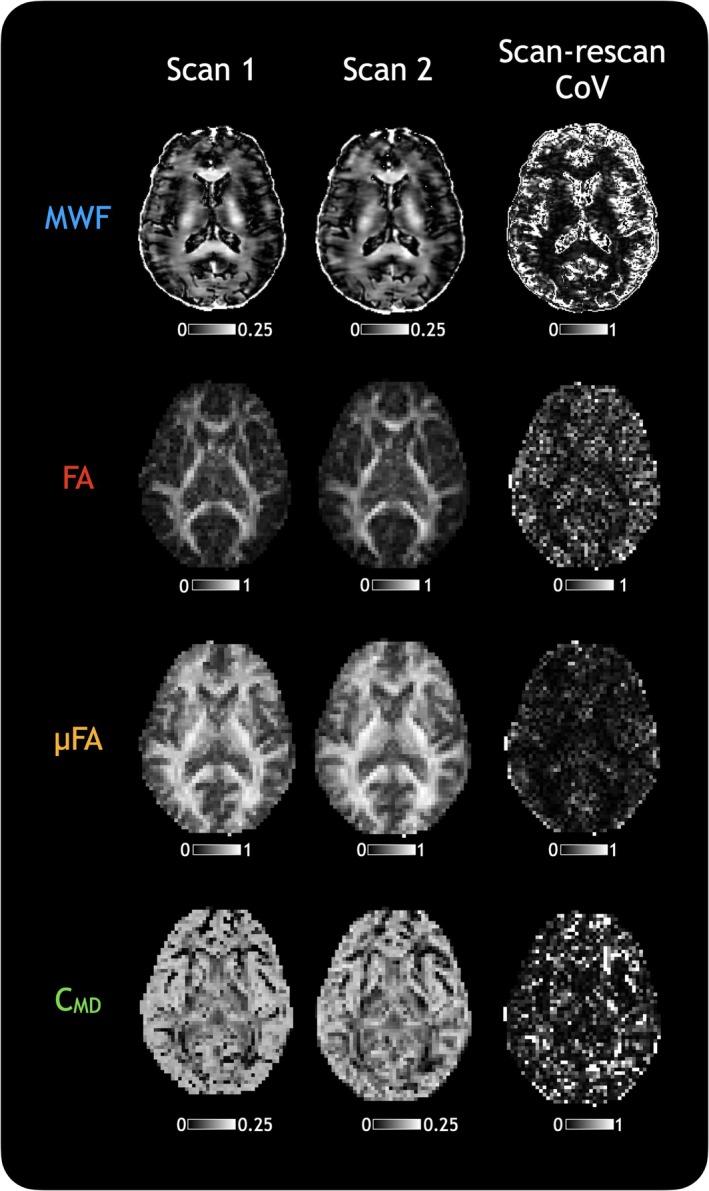

Conventional MRI offers limited insight into specific characteristics of central nervous system tissue, whereas quantitative MRI measures can provide more detailed information about different aspects of microstructure. A multi-metric approach involving multiple quantitative measures may improve our understanding of healthy tissue and pathology. Previous work shows myelin water fraction (MWF) is related to fractional anisotropy (FA), but this relationship is complicated by confounding factors that may be resolved using tensor-valued diffusion imaging, which yields measurements of microscopic FA (μFA) and tissue heterogeneity (C). Our aims were to better understand how measures from myelin water and tensor-valued diffusion imaging relate to one another, and to demonstrate how these measures can be used to characterize microstructure in both healthy white matter and pathological changes.

METHODS

We assessed the relationship between MWF, FA, μFA, and C from 25 healthy individuals through atlas comparison, correlation analysis, and tract profiling. We also applied z-score analysis and tract profiling in five people with multiple sclerosis (MS) to evaluate the multi-metric utility of these measures in assessing pathology.

传统磁共振成像(MRI)对中枢神经系统组织的特定特征的洞察有限,而定量MRI测量可以提供有关微观结构不同方面的更详细信息。一种涉及多种定量测量的多指标方法可能会增进我们对健康组织和病理学的理解。先前的研究表明髓磷脂水分数(MWF)与分数各向异性(FA)相关,但这种关系因混杂因素而变得复杂,这些因素可能可以通过张量值扩散成像来解决,张量值扩散成像可产生微观FA(μFA)和组织异质性(C)的测量值。我们的目的是更好地理解髓磷脂水和张量值扩散成像的测量值之间的相互关系,并展示如何使用这些测量值来表征健康白质中的微观结构和病理变化。

方法

我们通过图谱比较、相关性分析和纤维束剖析,评估了25名健康个体的MWF、FA、μFA和C之间的关系。我们还对五名多发性硬化症(MS)患者进行了z分数分析和纤维束剖析,以评估这些测量值在评估病理学方面的多指标效用。